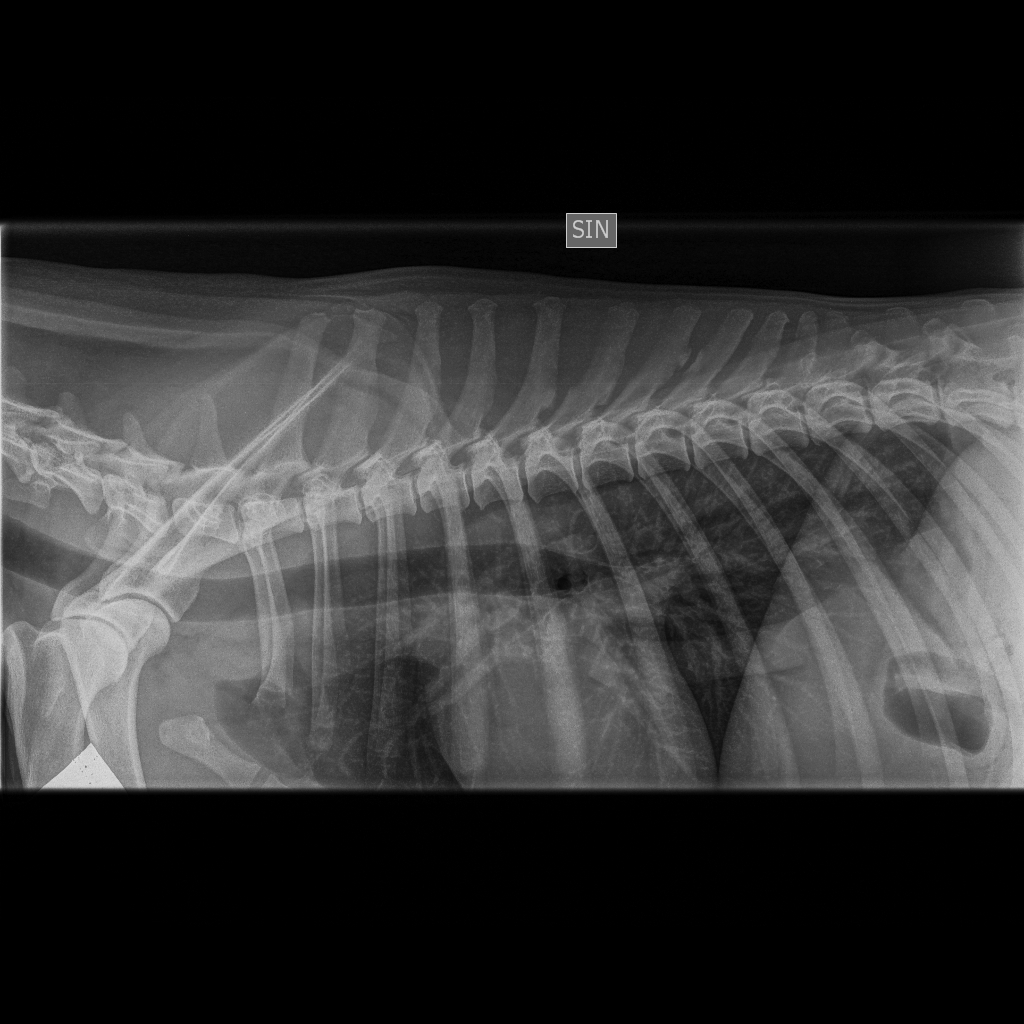

Viralliset selkäkuvat |

Muu luusto *) | Selkäranka, polvet ja olkapäät OK | Selkäranka ja olkapäät OK, polvet 0/0 | - | Selkäranka, polvet ja olkapäät OK | Selkäranka ja olkapäät OK, polvet 0/0 |

*) 6 koiran (muut paitsi Pikimusta ja Parfyymi) luustokuvaukset tehtiin 19.3.10 ell Kari Ventelän toimesta.

Parfyymin

luustokuvaukset tehtiin 7.6.10 ell Hannu Pajulahden toimesta.

Kuvatuissa nivelissä ja selkärangassa ei havaittu muutoksia.